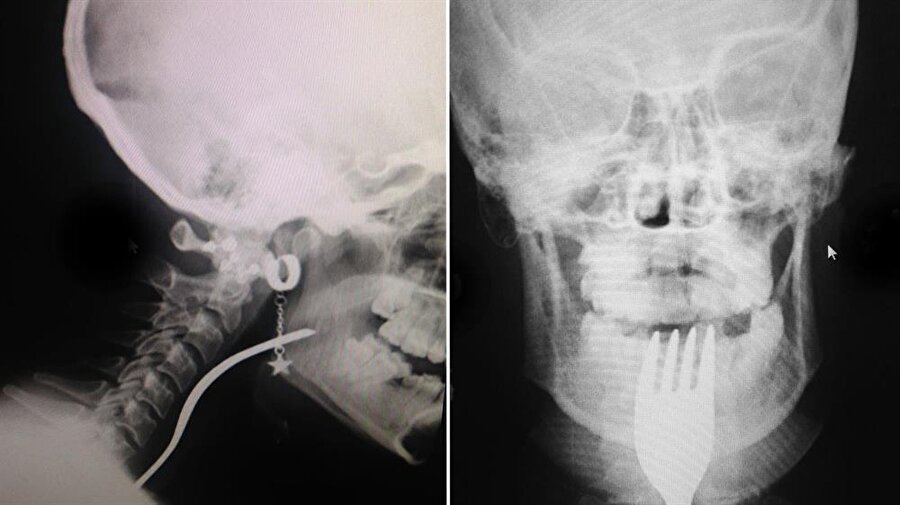

Bursa'nın Orhangazi ilçesinde bir genç kız, dişini karıştırdığı çatalın boğazına girmesiyle hastaneye kaldırıldı.

Alınan bilgiye göre, Üreğil Mahallesi'nde ailesiyle yaşayan 19 yaşındaki N.A, çatalın ters bölümüyle dişini karıştırmaya başladı. Bu sırada genç kızın boğazına çatal girdi.

Taksici babası İ.H.A. tarafından Orhangazi Devlet Hastanesine kaldırılan N.A, ilk müdahalenin ardından Uludağ Üniversitesi Tıp Fakültesi Hastanesine sevk edildi.

Burada yapılan müdahale sonucu genç kızın boğazına takılan çatal çıkarıldı.